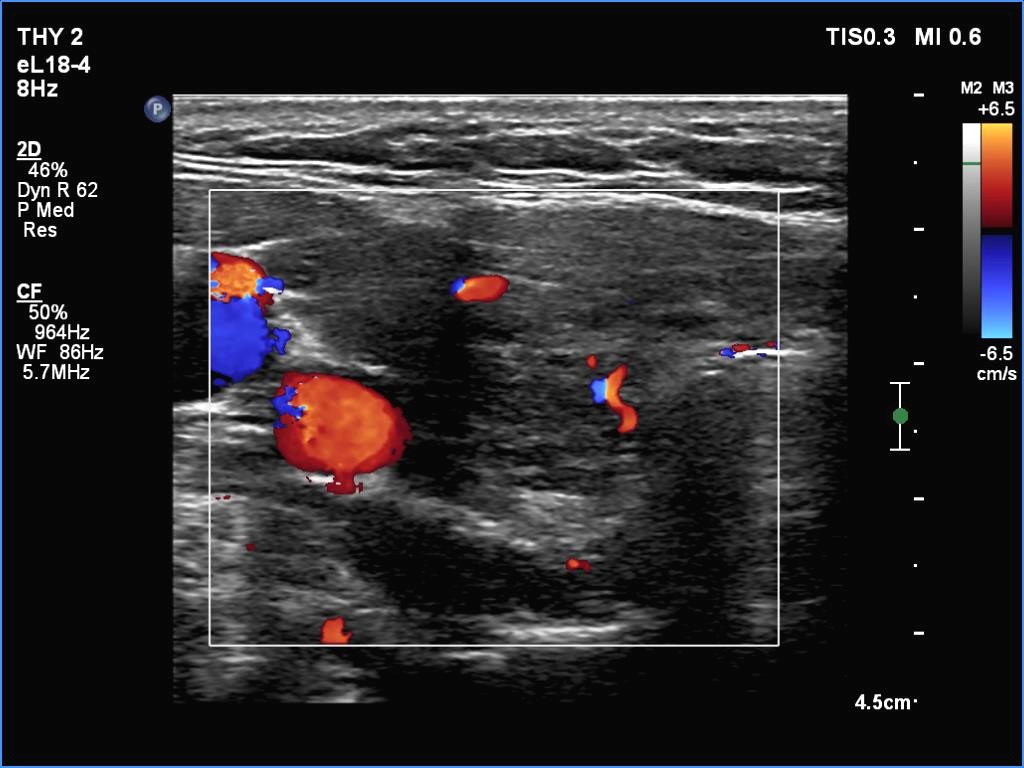

Right lobe, longitudinal scan

Right lobe, transverse view, color Doppler mode. Two large intrathyroidal vessels are shown.